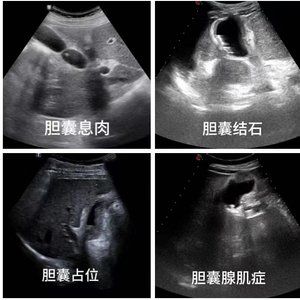

胆囊息肉,又称胆囊息肉样病变,是胆囊壁局限性增厚突入胆囊腔内的小结节样病变的总称。既往报道,我国人群体检胆囊息肉发生率2.68%~14.17%,近年来有逐渐上升的趋势。

胆囊息肉分为非肿瘤性息肉(假性息肉)和肿瘤性息肉(真性息肉)。非肿瘤性息肉大多属于良性病变,没有癌变倾向,包括胆固醇性息肉(最常见)、炎性息肉、增生性息肉以及少见的腺瘤样增生、黄色肉芽肿等。肿瘤性息肉又可分为良性和恶性,肿瘤性息肉有恶变的可能,据报道约6%胆囊癌源于息肉恶变。当然,莫要太担忧,肿瘤性息肉发病率只占到胆囊息肉的5%,而且迄今为止,未有非肿瘤性息肉癌变的报道。

超声检查是胆囊息肉的早期侦察兵。常规超声能清晰地显示息肉的大小,数量,位置,以及与周边脏器的情况。注意,胆囊的超声检查需要空腹,当空腹时胆囊内有足够的胆汁充盈,有利于清晰得显示胆囊的病变。而进食后,胆囊因胆汁排出后会缩小,无法清晰显示胆囊内的病变。因此胆囊的超声检查要强调“空腹”,一般禁食8小时以上。

当常规超声对鉴别肿瘤性息肉和非肿瘤性息肉有一定难度时,可运用超声造影技术,来提高胆囊息肉的诊断准确性。

超声造影,在常规超声基础上,通过静脉注射超声造影剂,可显示微小血管和低速血流,可实时动态观察胆囊息肉样病变内部的血流灌注情况,有助于对病变良恶性的鉴别诊断。一般来说,非肿瘤性病变内无超声造影增强,肿瘤性病变则有不同程度的超声造影增强。超声造影在息肉的定性上比CT和磁共振更具优势。

医生提醒:胆囊息肉是一种常见的疾病。如果您发现胆囊息肉,及时就医,早期诊断,结合息肉的大小、性质等制定科学合理的治疗方案。超声检查具有无创、经济、直观、便捷的优点,在胆囊疾病的鉴别诊断和治疗随访中具有重要价值,超声是胆囊息肉首选的影像学检查方法。